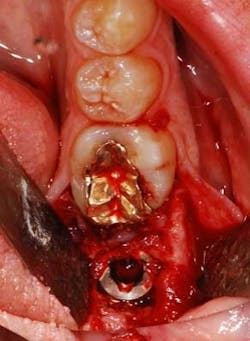

Fig. 2: Extraction of the residual roots

Fig. 3: Placement of a Southern Implants MAX implant into the prepared extraction site

Fig. 4: Southern Implants MAX implant seated in the osteotomy